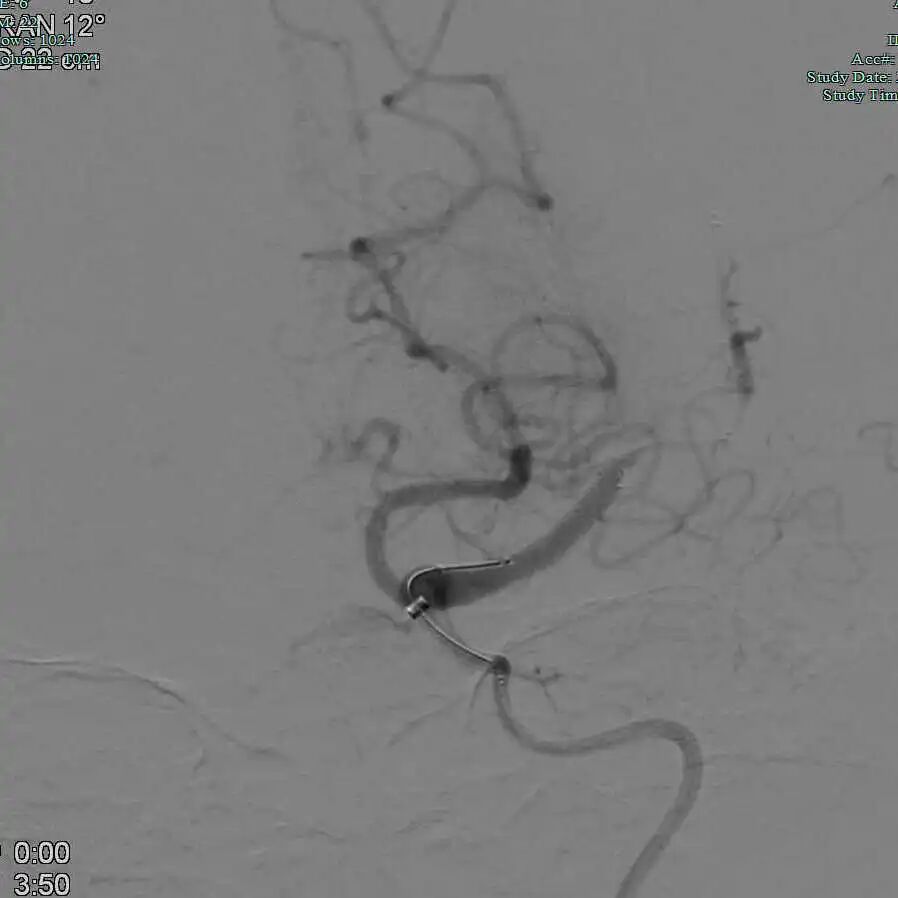

Tarvos微导丝携微导管超选大脑中上干,微导管冒烟确认血管真腔,释放取栓支架。

动脉长鞘怎么置入有励可说|Locaste 088励楷长鞘及Tarvos微导丝在左侧大脑中动脉闭塞取栓术中的应用_https://www.jmylbn.com_新闻资讯_第15张

动脉长鞘怎么置入有励可说|Locaste 088励楷长鞘及Tarvos微导丝在左侧大脑中动脉闭塞取栓术中的应用_https://www.jmylbn.com_新闻资讯_第16张

动脉长鞘怎么置入有励可说|Locaste 088励楷长鞘及Tarvos微导丝在左侧大脑中动脉闭塞取栓术中的应用_https://www.jmylbn.com_新闻资讯_第17张